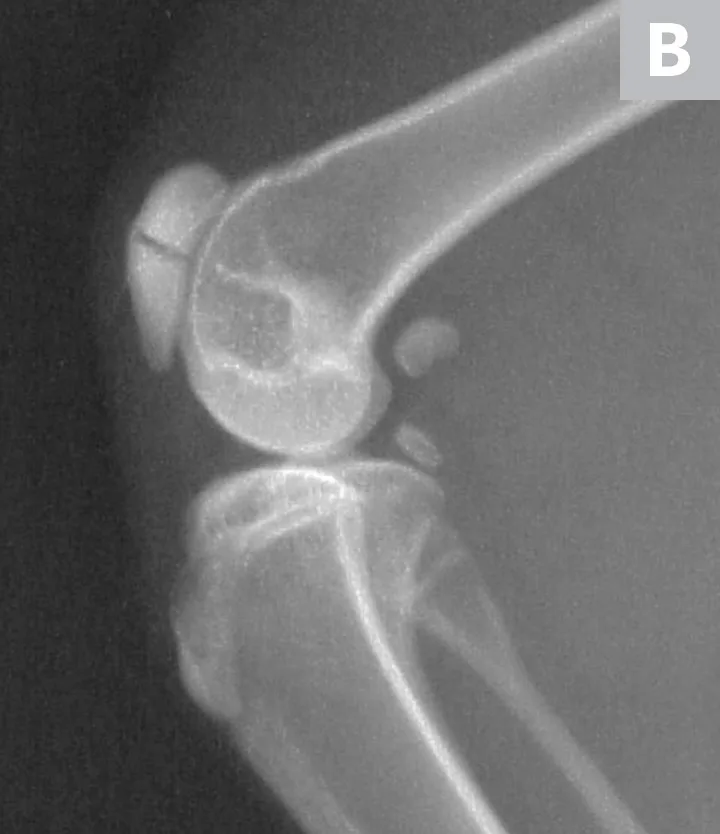

The patient received buprenorphine (15 µg/kg IV) for analgesia, followed by an induction with alfaxalone (0.5 mg/kg IV) and general anesthesia with isoflurane to facilitate dental and orthopedic radiography. Dental radiographs revealed persistent deciduous teeth and impacted permanent teeth. Lateral and craniocaudal pelvic limb radiographs revealed a displaced left patellar fracture and a nondisplaced right patellar fracture (Figure 2).

Lateral radiographs of the left (A) and right (B) stifles show a complete, displaced left patellar fracture and a nondisplaced right patellar fracture, respectively.